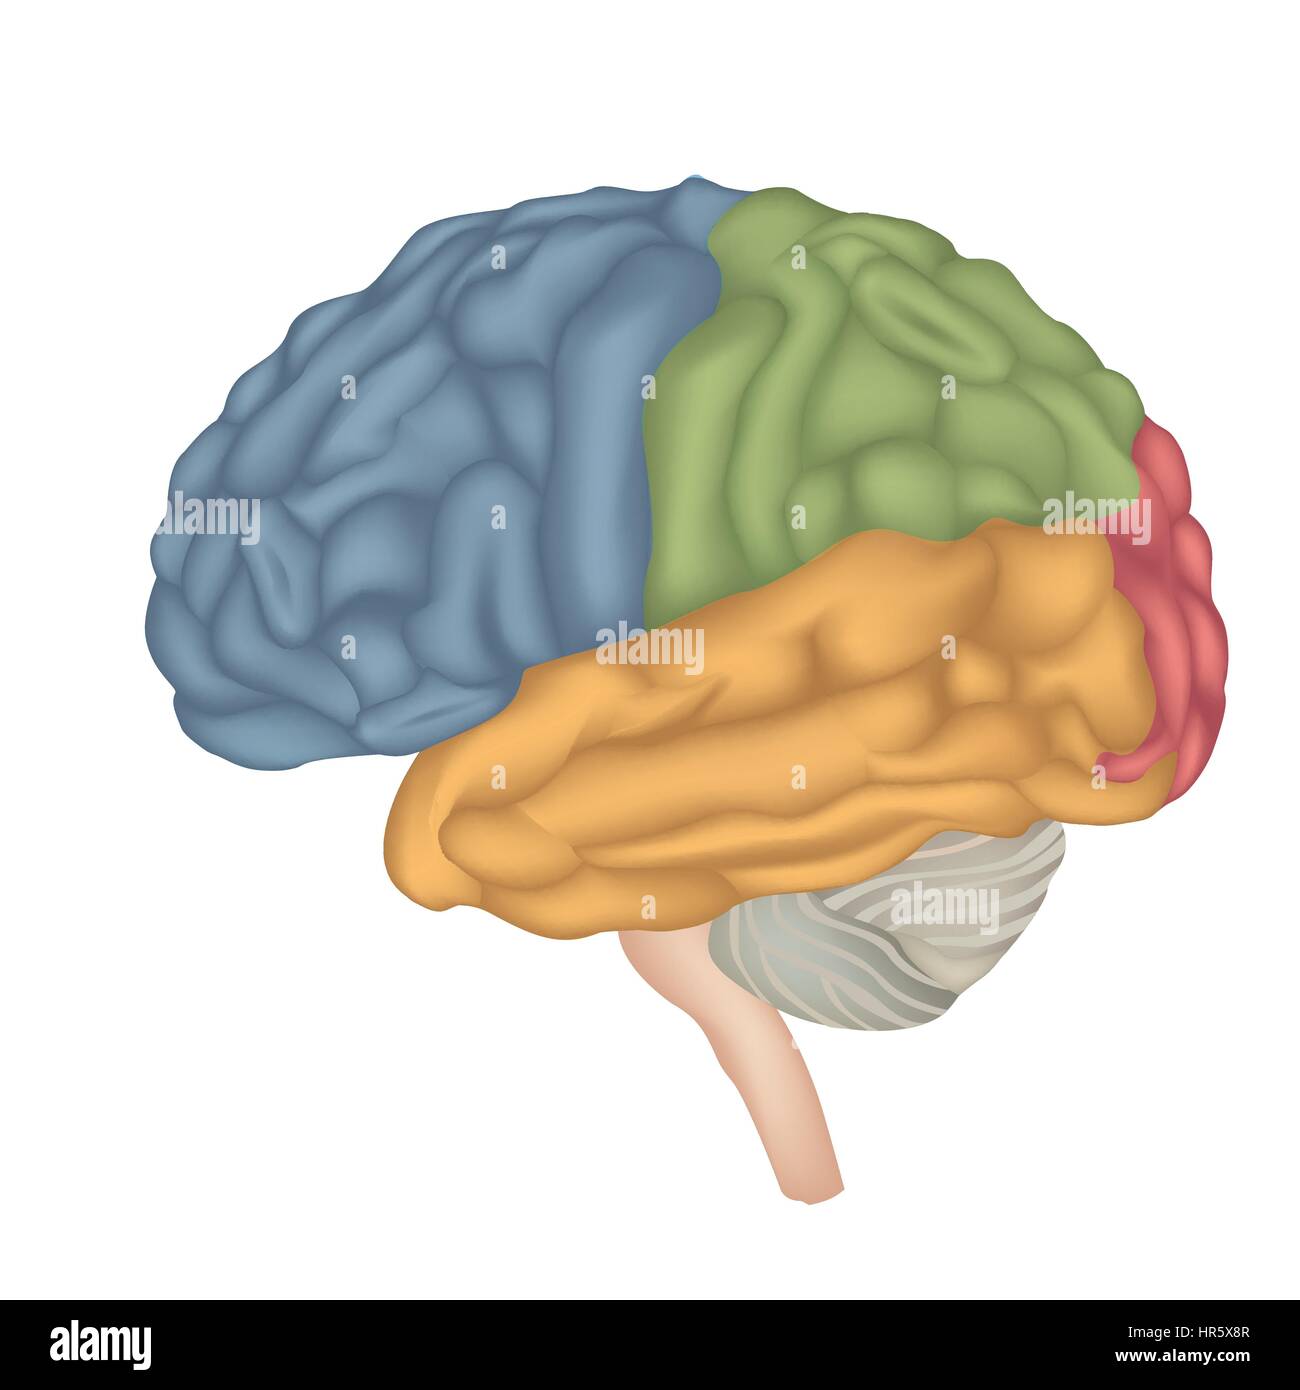

RF2R1KGAT–Struttura cerebrale umana. Emisferi e lobi della corteccia cerebrale. lobi frontali, temporali, occipitali e parietali. vista laterale e superiore

RF2Y8XEWG–Anatomia del cervello umano. Emisferi cerebrali, corteccia cerebrale, frontale, parietale, temporale, lobi occipitali, cervelletto e tronco cerebrale, fessura cerebrale.

RF2E374NN–Struttura dell'illustrazione della corteccia cerebrale. Regioni anatomiche colorate responsabili dell'intelligenza e del movimento.

RFTWMKBD–Aree funzionali del cervello umano. Assegnazione di aree in vista laterale del cervello. Illustrazione Vettoriale